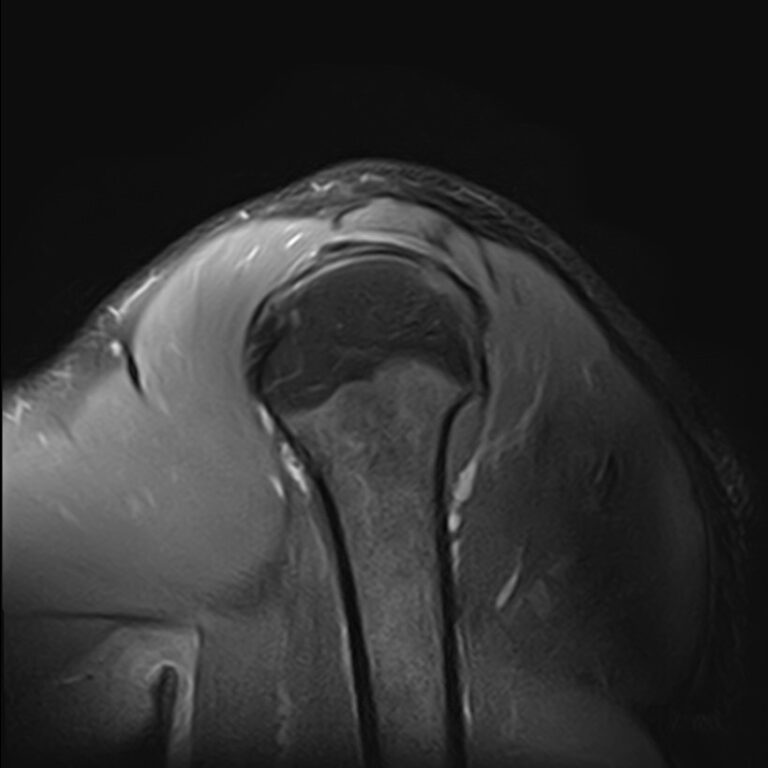

Плечевой сустав является наиболее подвижным сочленением, которое образовано лопаткой и головкой плечевой кости. У сустава нет мощных связок, он укрепляется мышцами плечевого пояса, окружающими его по типу корсета. Суставную капсулу образуют короткие связки, расположенные вокруг сустава. Благодаря такому строению сустав отличается высокой подвижностью, но при этом склонностью к вывихам. Полость сустава заполнена синовиальной жидкостью, питающей хрящи и служащей смазкой для них.

Метод МРТ позволяет оценить состояние всех анатомических областей плечевого сустава,  включая костную структуру, суставную капсулу, полость сустава с выстилающей его синовиальной оболочкой, связки, сухожилия, мышцы и окружающие мягкие ткани.